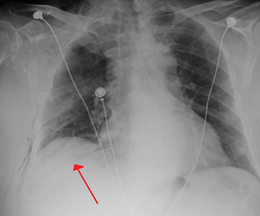

Chest tube

A chest tube (or intercostal drain) is the most definitive initial treatment of a pneumothorax. These are typically inserted in an area under the axilla (armpit) called the "safe triangle", where damage to internal organs can be avoided; this is delineated by a horizontal line at the level of the nipple and two muscles of the chest wall (latissimus dorsi and pectoralis major). Local anesthetic is applied. Two types of tubes may be used. In spontaneous pneumothorax, small-bore (smaller than 14 F, 4.7 mm diameter) tubes may be inserted by the Seldinger technique, and larger tubes do not have an advantage.[13] In traumatic pneumothorax, larger tubes (28 F, 9.3 mm) are used.[28]

Chest tubes are required in PSPs that have not responded to needle aspiration, in large SSPs (>50%), and in cases of tension pneumothorax. They are connected to a one-way valve system that allows air to escape, but not to re-enter, the chest. This may include a bottle with water that functions like a water seal, or a Heimlich valve. They are not normally connected to a negative pressure circuit, as this would result in rapid re-expansion of the lung and a risk of pulmonary edema ("re-expansion pulmonary edema"). The tube is left in place until no air is seen to escape from it for a period of time, and X-rays confirm re-expansion of the lung.[13][17][23]